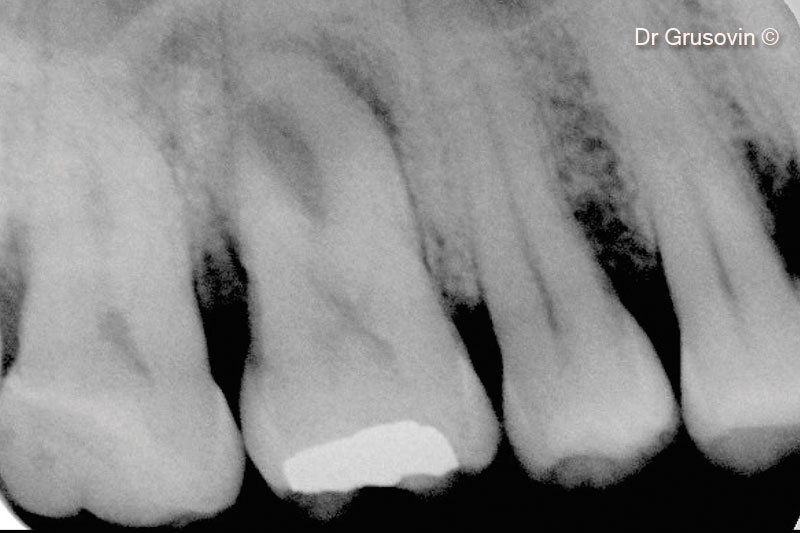

3. X-ray #16